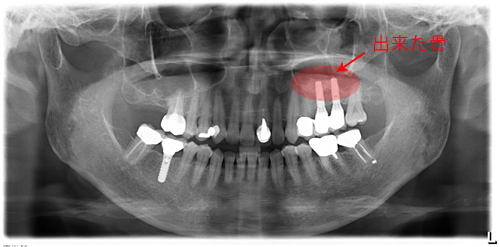

奥歯は骨が少なく、骨をつくり、インプラント治療をしました。赤く囲ったところが出来た骨です。